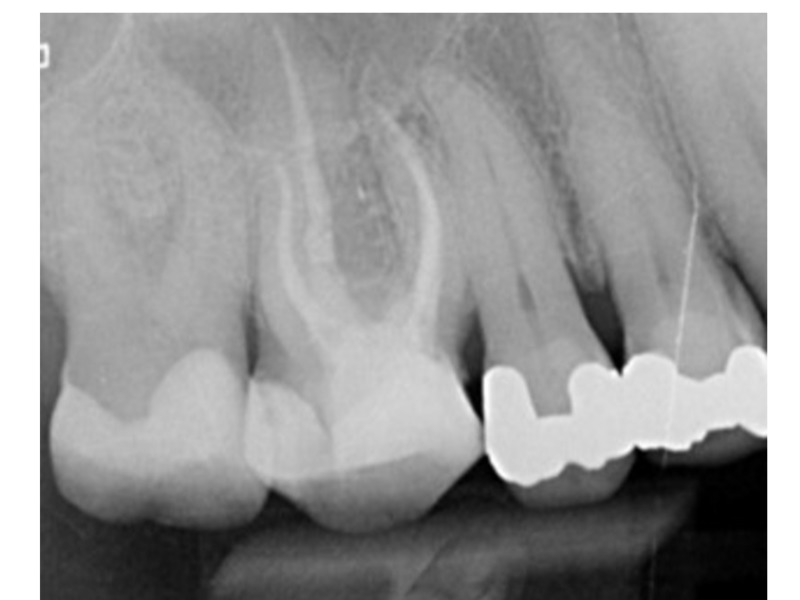

• Čtení RTG snímků, CT vyšetření

• Výrazně zahnuté kořenové kanálky

• Obliterované kořenové kanálky